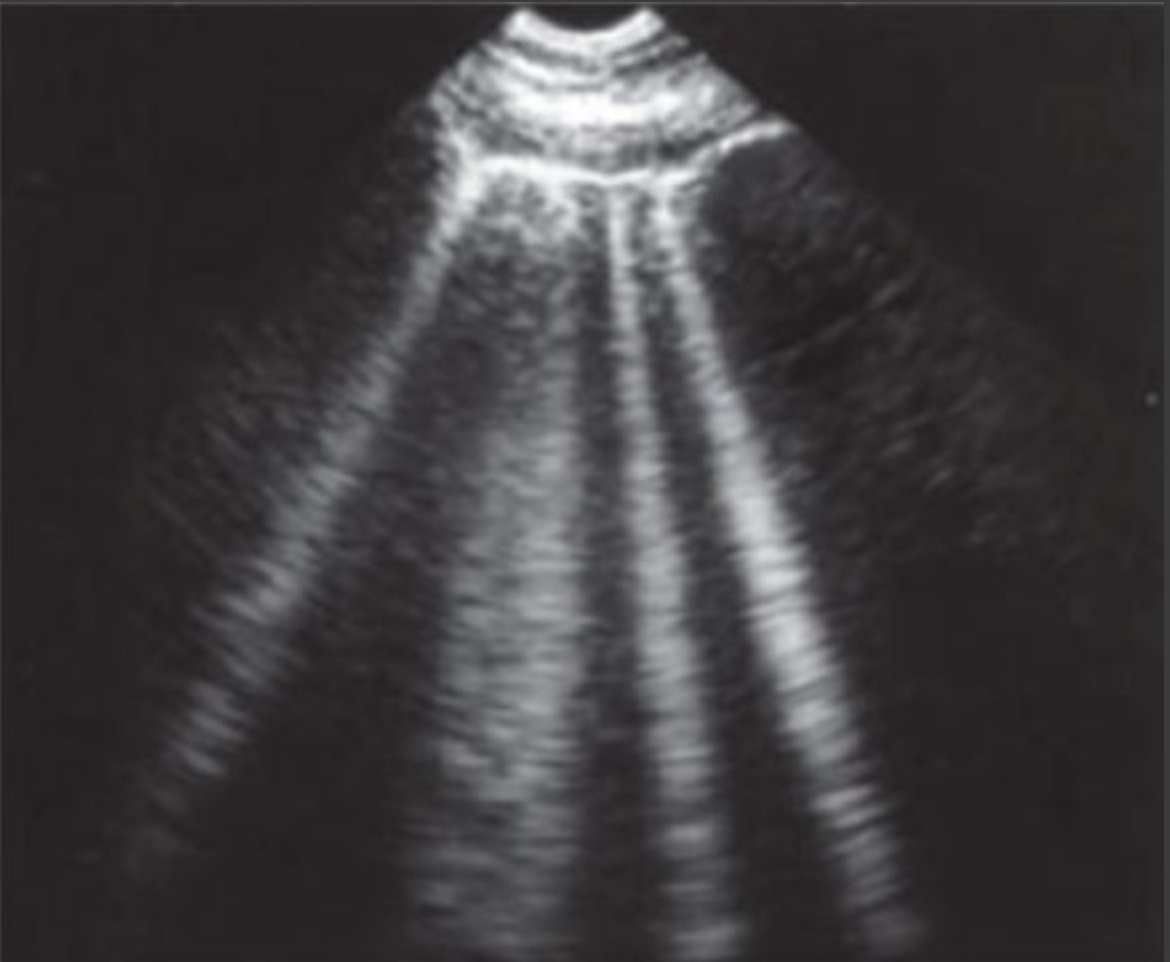

19.1 Paeditric cxr with history of congential heart disease repair and what was the repair based on the cxr: A) Av repair B) Pv repair C) ASD closure device D) Parachute device E) Right atrial appendage closure device

C) ASD closure device